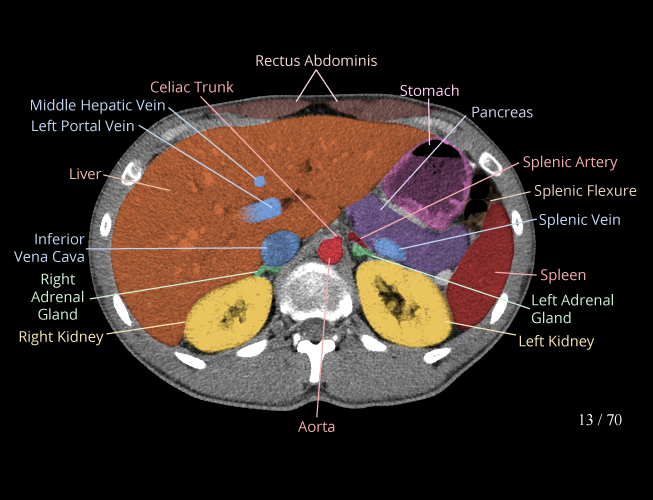

Body

Covers abdominal CT anatomy.